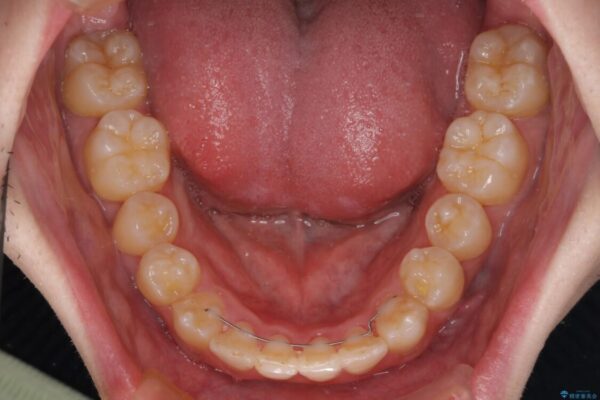

治療後

• 全顎的なクロスバイト 補助装置を用いてワイヤー矯正 治療後画像